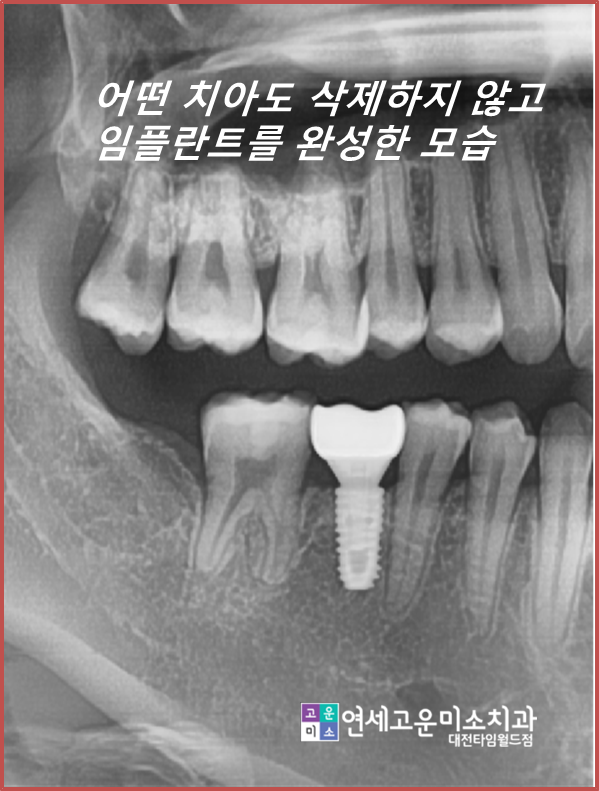

완성된 모습입니다

쓰러진 치아도 세워졌고

임플란트도 옆의 치아들 뿌리와 평행하게

심을 수 있게 되어 저작에도 유리한 상황입니다.